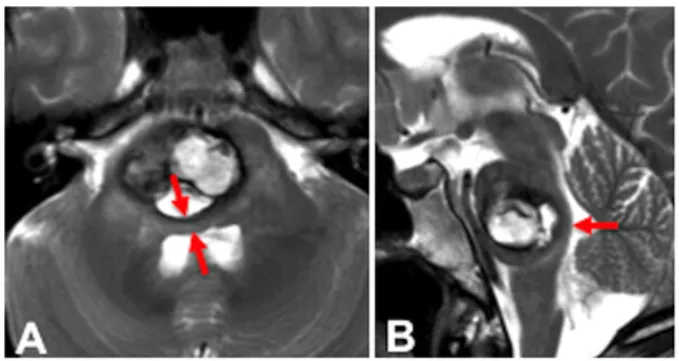

46岁女性患者突发左侧面部麻木症状。影像学检查显示大型出血性轴内桥脑海绵状血管瘤(图A和B)。脑桥背侧结构受压明显(红色箭头指示),提示病变与菱形窝表面间仅存薄层脑实质。

该患者选择手术治疗,巴教授采用乙状窦后经小脑幕入路实施开颅手术。术中完整保留三叉神经(CN V)和耳蜗神经(CN VIII);该区域被选为脑桥入口点,两条神经均获完整保留。患者术后恢复平稳,未出现其他神经系统并发症。

术后影像记录切除情况,病灶实现全切(图D和E)。减压后,切除腔背侧脑桥实质明显展开并恢复原有宽度(红色箭头)。